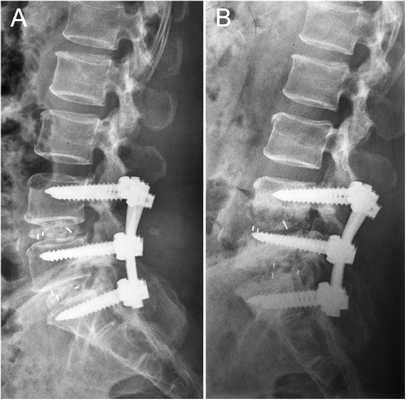

заведение канюлированных винтов проводилось под контролем электронно-оптического преобразователя в трех плоскостях - обзорный фасный снимок (рис. 1), краниальная (рис. 2) и каудальная (рис. 3) проекции. Это позволяет избежать повреждения сосудисто-нервных образований, располагающихся кпереди и кзади от ножки и тела s1 позвонка.

Стабилизационная система на рентгене.

Стабилизация поясничного отдела.